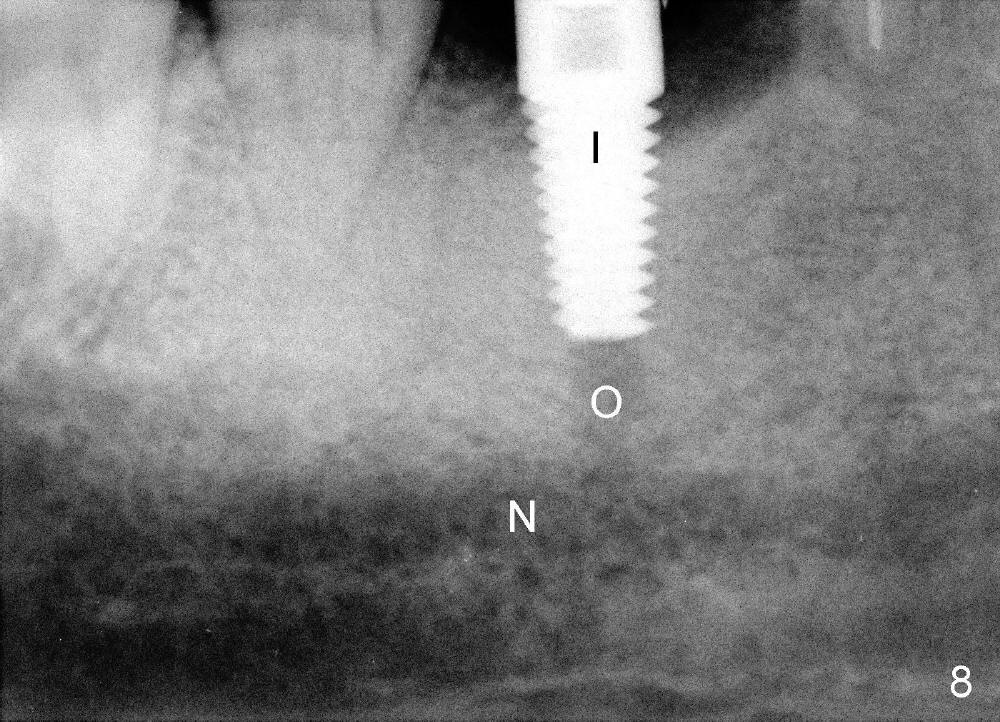

When the pilot drill is inserted into the initial osteotomy site for X-ray confirmation of its depth (Fig.7: D), the vertical block of the endo device (yellow rectangle) may be blocked due to the narrow divided edentulous space. The crown of the molar is shown, whereas the inferior alveolar nerve is not shown except a small portion in the left lower corner of Fig.7 (pink line). The depth of the further osteotomy (Fig.8: O) was chosen without accurate estimate. The integrity of the inferior alveolar canal (IAC) was violated, although the implant (I) was not placed that deep. The patient experienced transient postop pain, which was controlled by Medrol Dosepak. A correct way to prevent iatrogenic neuropathy in this situation is to remove the pilot drill, and place the endo device as deep as possible. The new X-ray should be able to reveal the relationship of the end of the osteotomy (shadow) to IAC. Measurement must be done using digital X-ray software over the new image to determine how deep osteotomy should be made (as shown in Fig.10). When an implant is placed (I in Fig.9: a second case as will be shown in Fig.10-12), the vertical block of the endo device can be placed on the implant. The sensor is placed deep into the lingual vestibule to show IAC in relation to the implant (Fig.8).